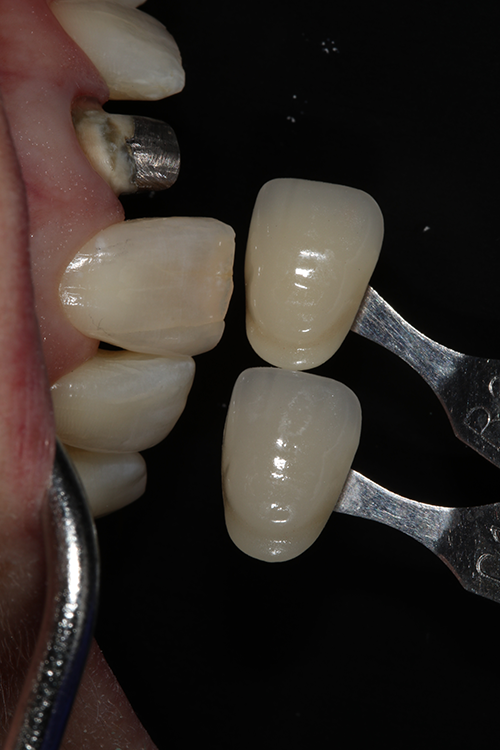

A preoperative impression was taken and a wax-up was made, after which a silicone matrix (Sil-Tech, Ivoclar Vivadent) was made from the wax-up for use in creating a direct provisional restoration. The old crown restoration was sectioned off, and the preparation was refined using a series of preparation burs (Dr. Robert Winter Restorative Design Bur Block, Brasseler USA). Final impressions were then taken using a vinyl polyether silicone (VPS) impression material that demonstrates intrinsic hydrophilicity and optimal flow and tear strength (EXAl’ence™, GC America) (Fig. 3). Stumpf shades were taken using a stumpf shade guide (Ivoclar Vivadent) (Fig. 4), and the tooth shade for fabricating the restoration was determined using a standard VITA shade guide and VITA 3D-Master Shade Guide against the adjacent natural tooth #8 (Figs. 5 and 6).